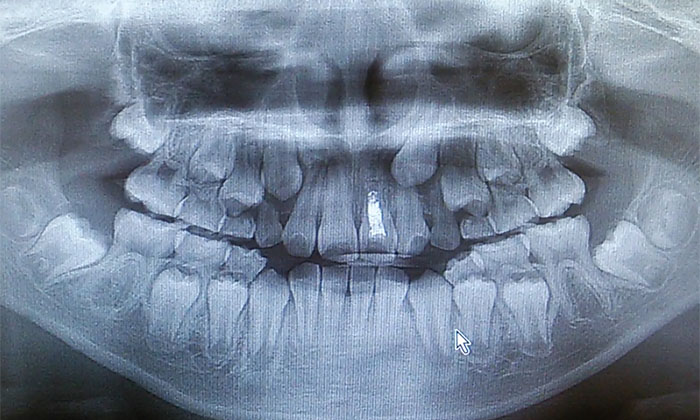

いつまでも生え変わらない時にはレントゲン撮影をして確認すると良いですね。

1. 乳歯の下では、永久歯になるための「歯胚」ができて少しずつ成長します。

2. 永久歯の咬む部分ができて歯の根の部分ができ始めると乳歯を少しずつ吸収していきます。

3. 乳歯の根の部分が無くなるとグラグラして永久歯が出てきます。